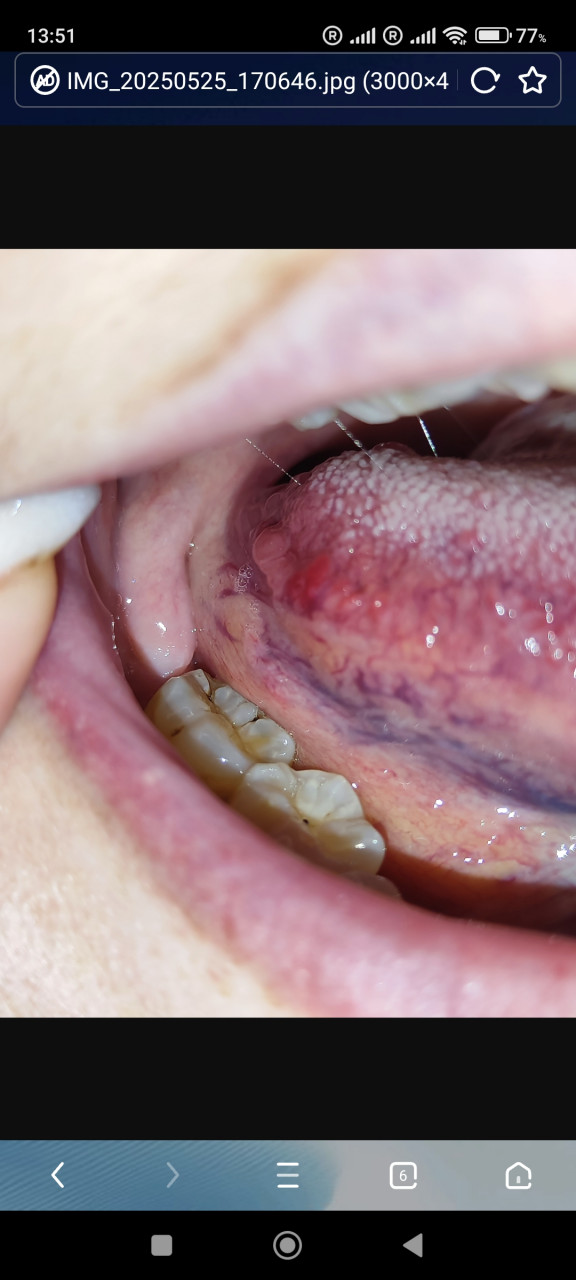

Боковая поверхность языка

Здравствуйте! Уже больше месяца на боковой поверхности вот такие наросты. Иногда ощущение жжения. Что это такое? Опасно ли? Спасибо!

43

Гастрит